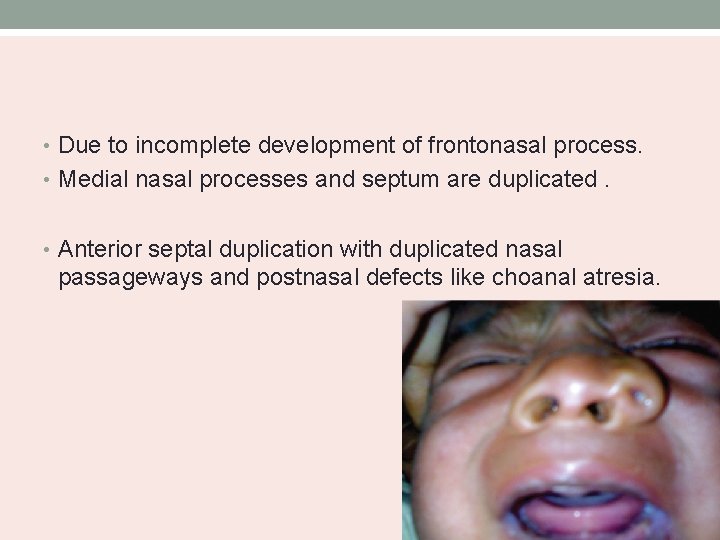

Polyrhinia and Supernumerary nostril • Double nose with accessory nostril. • Associated with pseudohypertelorism.

• Due to incomplete development of frontonasal process. • Medial nasal processes and septum are duplicated. • Anterior septal duplication with duplicated nasal passageways and postnasal defects like choanal atresia.